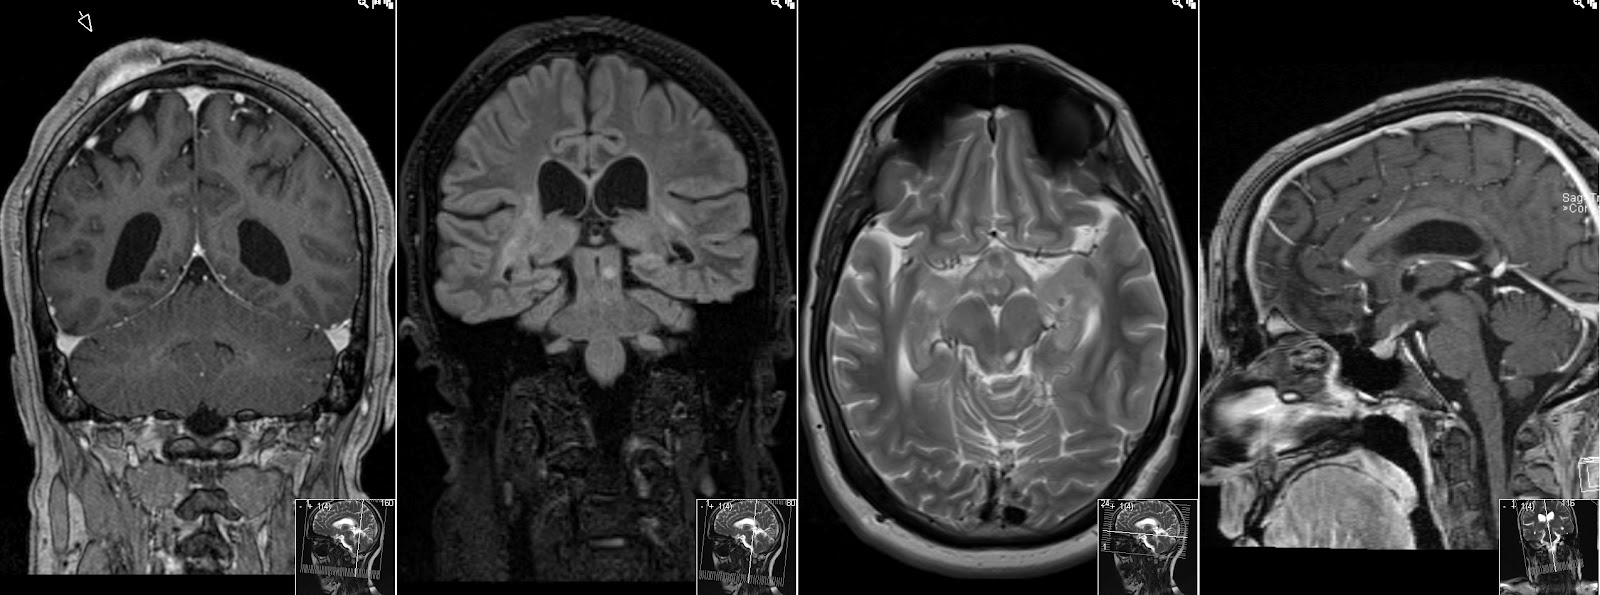

This patient is known with Neurofibromatosis Type 1 (von Recklinghausen Disease). Note enlarged optic nerves on coronal T2, as well as thickened optic chiasm on coronal T1 with Gadolinium and thickened optic tracts on transversal T1 with Gadolinium. This is due to Optic Glioma. There is very little, almost no contrast enhancement. Last image, transversal T2, showing tumor infiltration in the optic tract as well as Focal Areas of Signal Intensity (FASI) - that show no enhancement.

Also note enhancing Subcutaneous Neurofibroma, more FASI and how the thickened optic chiasm looks on sagittal T1.